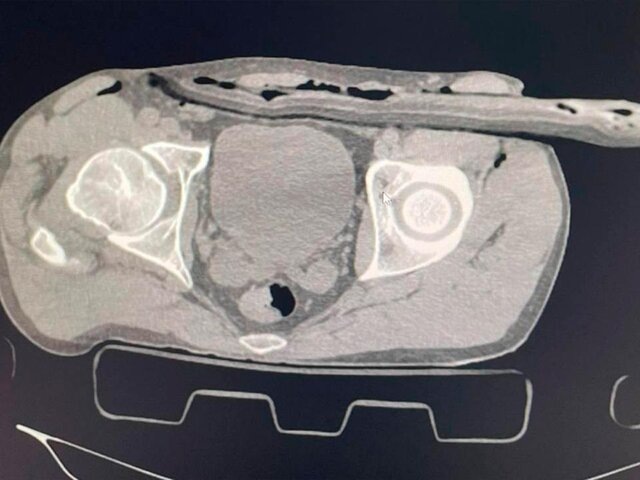

Фото: телеграм-канал "Разборчивым почерком"

Пострадавший ремонтировал крышу загородного дома без страховки и упал на сук. Ветка прошла через бедро в толщу брюшной стенки. В больнице ему сделали компьютерную томографию и УЗИ, которые показали наличие свободной жидкости в животе.

Врач-хирург Солнечногорской больницы Иван Балычев отметил, что ветка не задела важные артерии и органы брюшной полости. В ходе операции, которая длилась около часа, медики ушили дефект в брюшине, провели ревизию органов брюшной полости, а также сделали дренаж раневого канала.